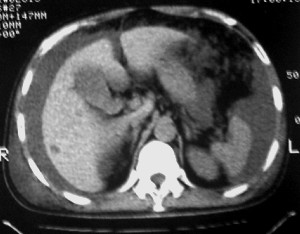

m ,60岁,右上肺ca术后一月。

右侧肺癌术后:肝内可见多个大小不等的低密度结节影。腹腔及双侧胸腔大量积液。考虑:肺癌并胸膜及肝脏转移。

腹水,肝及右肾多发低密度影。考虑转移。

肝及右肾转移瘤,双侧胸水

右肾及肝内多发转移瘤,胸水。